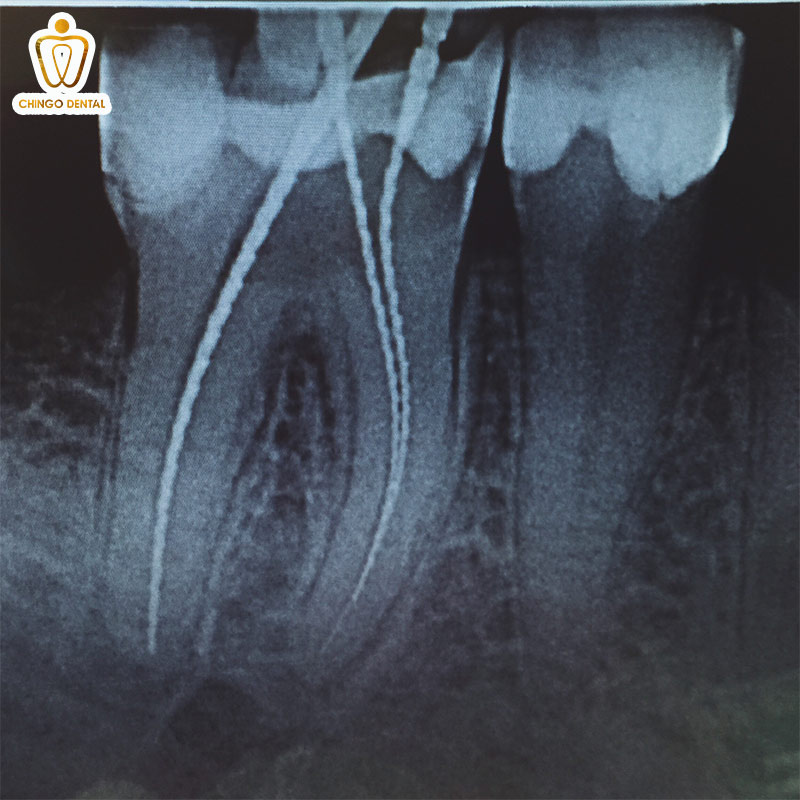

Phim cận chóp: Cái nhìn chi tiết đến từng chân răng

Phim chụp X-quang 1 răng là loại phim nhỏ gọn và phổ biến nhất tại phòng khám. Bác sĩ sẽ đặt một tấm phim nhỏ ngay sát chiếc răng bạn đang bị đau. Đoạn phim chụp X-quang răng này giống như một bức ảnh “chụp chân dung” cận cảnh. Giúp bác sĩ quan sát rõ nét từ đỉnh răng xuống tận gốc chân răng đang nằm sâu trong xương hàm.

Nếu bạn đang bị sâu răng hay viêm tủy, chụp phim răng là cách nhanh nhất để bác sĩ tìm ra nguyên nhân và xử lý ngay lập tức.